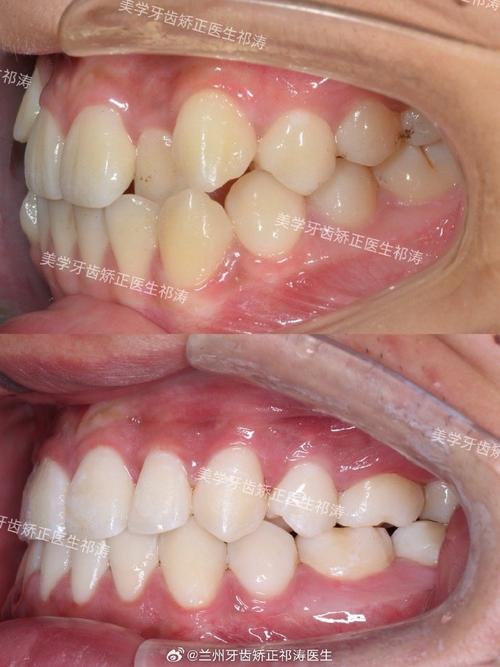

- 最常用且有效的解决方案。 如果拥挤的主要原因是缺牙后邻牙倾斜、对颌牙伸长、或其他牙齿移位导致的排列不齐,正畸治疗是首选。

- 目的: 将倾斜的邻牙扶正,将伸长的对颌牙压低(可能需要配合牙冠或嵌体降低高度),将移位的牙齿排列整齐,建立稳定、协调的咬合关系。

- 方式: 可以选择传统固定矫治器(钢牙套)、陶瓷矫治器、隐形矫治器(如隐适美、时代天使)等,矫正方案需要考虑种植牙的存在,设计时可能需要特殊处理(如种植体支抗)。